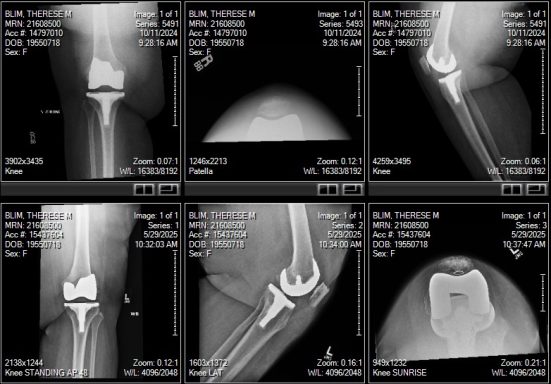

In this series, medical scans—MRI images, X-rays, and other diagnostic views—are transformed into intimate portraits that merge the clinical with the deeply personal. Each work intertwines medical imagery with biographical details, creating a layered visual narrative that honors both the physical realities of illness and the inner lives of those who endure them.

The exhibition features representations of conditions such as multiple sclerosis, lung cancer, hip and knee replacements, a broken wrist, miscarriage, and heartache—each one a story of endurance, adaptation, and faith. The artist wishes to express her gratitude to the patients and their families who entrusted her with creating artworks as unique and special as they are while acknowledging that recovery is never an individual journey; it extends to loved ones who must also heal, grieve, and rediscover vitality in the face of loss or uncertainty.

Mixed media pieces of art derived from the combination of medical scans, surveys from family and friends and genuine creativity from the creator, these artworks are one of a kind.